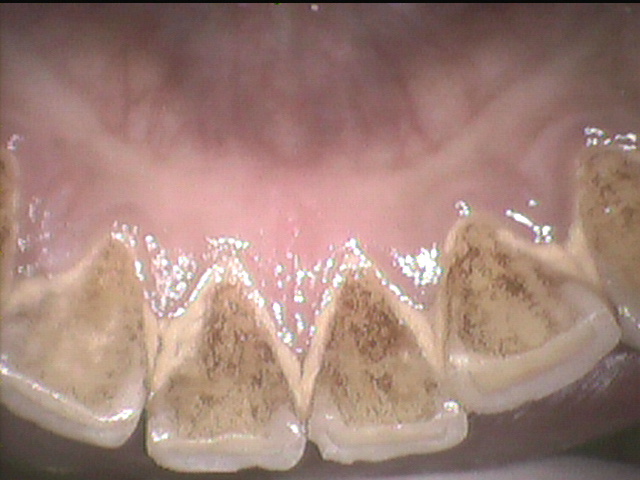

11月が最終日となる本日は歯の面が下で触るとざらざらして気になるという患者様がご来院されました。

下で気になる部分の歯を触れてもらうとアマルガムという充填物がざらついており寿店物の周囲に腐食と不適合を生じていました。

患者さんに説明してアマルガムという水銀を含む充填物を除去してその周りにできた虫歯も綺麗に取り除きました。